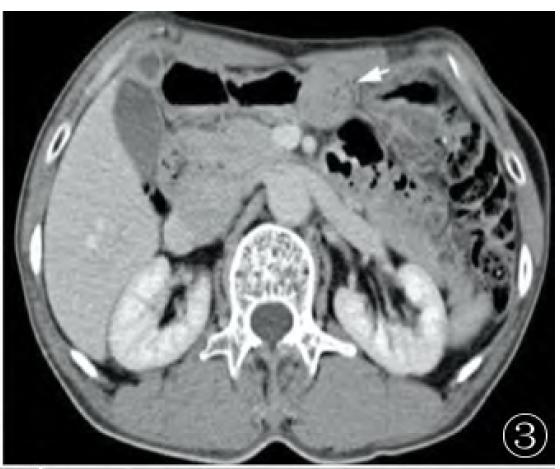

胃血管球瘤影像表现

位置:胃窦部;

大小、形态和质地:均较小,直径多小于 3cm,类圆形或椭圆形,边界清晰, 实性结构的软组织块,且均为实性结构,未见囊性改变;

肿块位于胃黏膜下,实质密度较均匀,平扫约30-40HU,未见坏死及囊变,病灶表面可见溃疡, 病灶内可见小点状钙化;

增强扫描表现:动脉期、门静脉期和延迟期均呈明显强化,动脉期肿块周边可见有结节样强化或均匀强化,门静脉期和延迟期仍有明显强化,强化程度类似于门静脉、下腔静脉,甚至与降主动脉类似;

经典型胃血管球瘤与肝脏海绵状血管瘤强化方式类似,动脉期局部或周边出现絮片状强化,门脉期进一步均匀强化,强化峰值通常出现在门脉期,CT值与同层腹主动脉相近,延迟期持续强化;

血管瘤型胃血管球瘤强化峰值可出现在动脉期,门脉期及延迟期持续均匀强化。